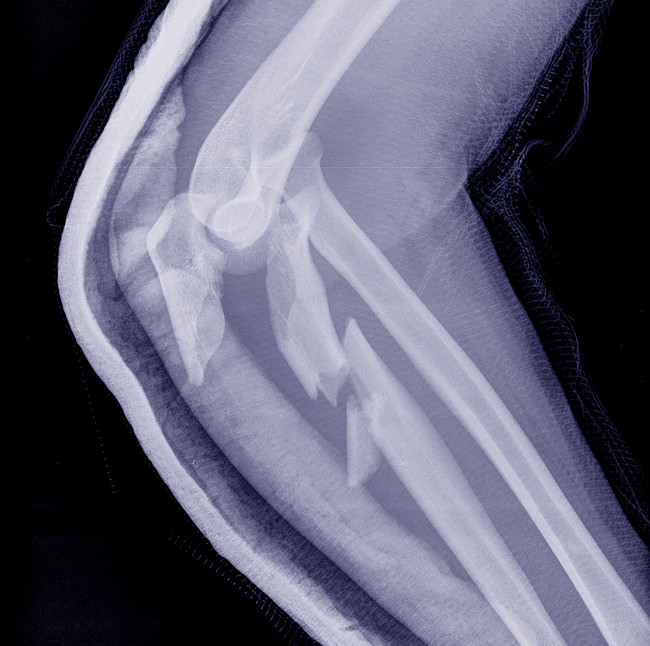

Дистальные переломы

Дистальный перелом – это повреждение нижнего конца плечевой кости, чаще всего в области локтевого сустава. Такие травмы нередко затрагивают суставную поверхность, что делает их более сложными для лечения. При незначительном смещении врач может назначить консервативное лечение и гипсовую повязку, но при внутрисуставных травмах требуется хирургический остеосинтез с анатомическим восстановлением суставной поверхности.

Надмыщелковые и мыщелковые переломы

Эти типы травм наблюдаются преимущественно у детей и молодых людей при падении на согнутую руку. Надмыщелковый – расположен выше суставной поверхности, а мыщелковый – затрагивает ее частично. Лечение направлено на восстановление формы сустава и предотвращение контрактур. Применяется гипс при переломе плеча, при необходимости выполняется репозиция под контролем рентгена.

Чрезмыщелковые переломы

Самые сложные повреждения, при которых линия перелома проходит через оба мыщелка, разрушая суставную поверхность. В таких случаях консервативный метод малоэффективен – требуется хирургическое лечение. Врач проводит остеосинтез специальными мини-пластинами и винтами, добиваясь точного сопоставления отломков. После операции назначается этапная реабилитация и физиотерапия для восстановления объема движений в суставе.